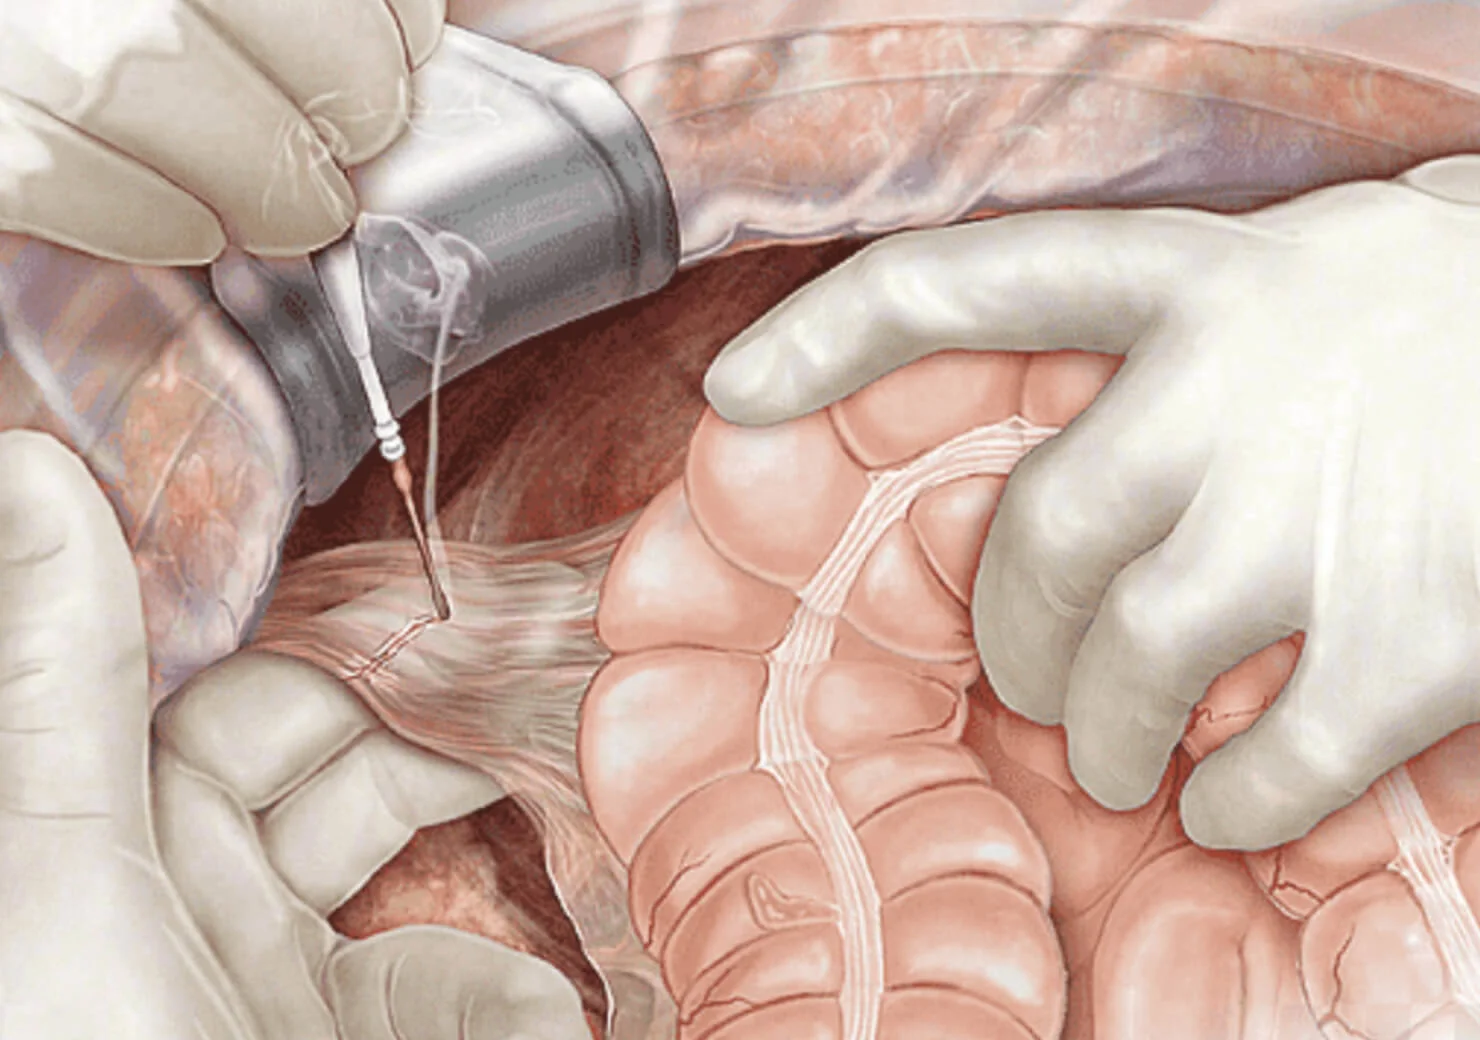

- Colectomia